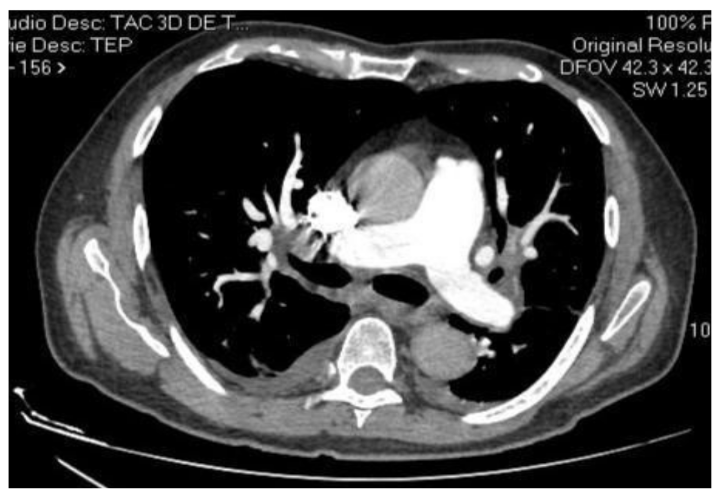

El paciente es valorado por el servicio de Nefrología, el cual ordena hemodiálisis diaria, con sesiones de 4 horas cada una, sin heparina y volumen de 350 ml/min - ultrafiltrado de 3000 cc. Posteriormente, el paciente presentó exacerbación de la disnea y se solicita dímero D con reporte de 700, ante lo cual se complementa con una angiotomografía de vasos pulmonares (angiotac), de acuerdo con el protocolo para tromboembolismo pulmonar (TEP) con reporte negativo para TEP (figura 3). Adicionalmente, se realizaron laboratorios de control creatinina en suero: 9,23 mg/dl, potasio: 5,33 meq/l, sodio: 138 meq/l, hematocrito: 36,7 %, hemoglobina: 11,2 gr/dl, leucocitos: 11.590, neutrófilos: 80,9 %, plaquetas: 275.000 y HBA1C fuera de metas (9,5 %), lo que aumenta su riesgo cardiovascular.